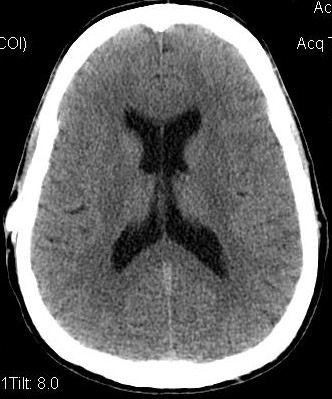

Below, are my CT images beginning on Jan. 17, 2011, where there is enlargement of the ventricles, followed by further enlargement on April 9, 2011, and what appears to be more enlargement on June 8, 2011, despite my May 23, 2011 revision. Then, there appears to be a slight decrease in ventricular enlargement on June 20, 2011, followed by normal size (almost too small) ventricles on July 23, 2011. We felt my ventricles came down in size too quickly, and began to raise the proGav setting over a period of two months, eventually up to 6, and rescanned me on Sept. 15, 2011. Those results indicated my ventricular enlargement had returned, so the proGav was returned to a lower setting of 2.

In hindsight, perhaps one mis-step we made was in not obtaining a CT scan right before surgery so as to have a true baseline. My headache, nausea, memory, and balance symptoms had worsened from April 9, 2011 to May 23, 2011, and I had lost appetite and weight. A CT on the revision date would have likely shown considerably more ventricular enlargement as compared to April 9th, rendering the post op CT of June 8, 2011, an improvement, instead of a worsening as we thought. I was having ongoing headaches upon waking in the a.m. and during the daytime after the proGAV revision, with no improvement in memory, and no apparent improvement on CT compared to April 9th, and requested that the proGAV to be lowered all the way to 0 only a few weeks post op. Despite programmable shunts having been in use since 1999, there still remains some considerable confusion and miscalculation in achieving the most optimal settings, and I remain dissatisfied with industry's inattentiveness to this issue. I also think this lack of attentiveness speaks to the high number of unofficial reports of accidental reprogramming of (Codman & Medtronic) programmable shunts. Of course, with the addition of a locking pin on the proGAV valve, this is unlikely to be an issue.

Under my CT images below, I list each of the proGAV's corresponding settings. It was initially set at 10 during surgery, with no improvement in complaints after one week, I asked that it be lowered to 7, and one week later to 5, then to 3, and finally to 0. During this period, almost every morning I awoke with a substantial headache that I assumed was due to increased ICP and underdrainage. On the June 20, 2011, CT we could finally see some decrease in the dilation of my ventricles, and determined the shunt to be working. But, we were still puzzled by the ongoing awaking a.m. headaches. For this reason, it was temporarily raised to a setting of 2, and then with no relief back down to 0. It remained at 0 for almost a month when the July 23, 2011 scan revealed normal sized ventricles.  Because of the relatively short period it took for my ventricles to come back to normal, we raised the proGAV gradually to 6, and back down to 2 after the Sept. 15, 2011 scan showed a return of ventriculomegaly.

Jan 17, 2011 OSVII                    April 9, 2011 OSVII                 Shunt Revision to proGAV May 23, 2011

June 8, 2011 proGAV  5/20    June 20, 2011 proGAV 3/20      July 23, 2011 proGAV 0/20    Sept. 15, 2011 proGav 6/20   Feb. 1, 2012 proGav 0/20